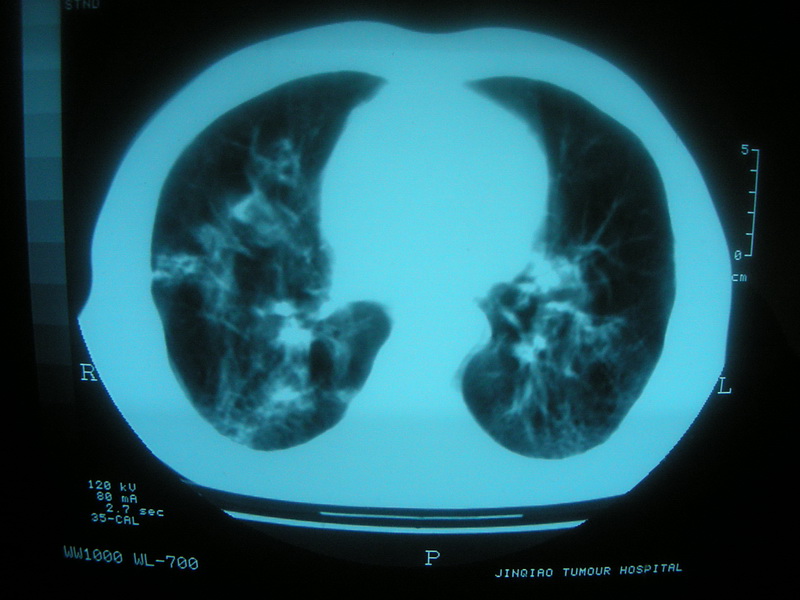

标题: CT11692:男,63岁,糖尿病史15年.抗炎治疗7天,病情 [打印本页]

标题: CT11692:男,63岁,糖尿病史15年.抗炎治疗7天,病情

请老师看看是结核还是炎症?

双肺继发性肺结核伴感染!

双肺继发性肺结核伴支气管播散。

考虑双肺继发性肺结核。